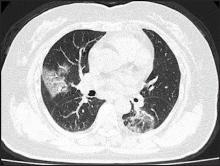

February 28, 2020 — The first in a series of medical imaging studies on novel coronavirus (COVID-19) was published online ahead of print this week by the American Journal of Roentgenology (AJR).